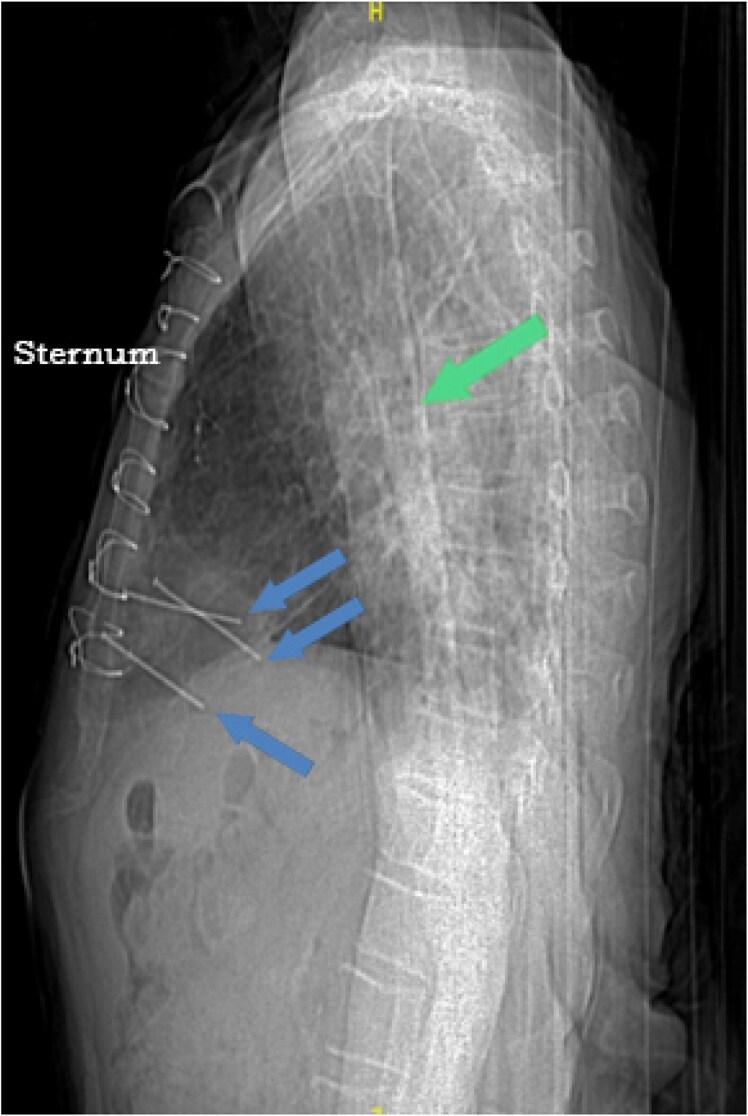

A frail 83-year-old male who had undergone coronary artery bypass grafting surgery 20 years ago presented with encephalopathy. He had persistent bacteraemia. Chest computed tomography revealed three metal nails penetrating the anterior thoracic wall through the myocardium. Later, we learned that he had attempted suicide 2 years ago by shooting himself in the chest using a nail gun. Conservative non-surgical approach was pursued at that time given his multiple comorbidities. We adopted a conservative approach again. He survived for additional 6 months on chronic suppressive antimicrobial therapy but ultimately passed away from pneumonia.

一名83岁体弱男性,20年前接受过冠状动脉搭桥手术,现出现脑病。他持续存在菌血症。胸部计算机断层扫描显示三根金属钉穿过心肌穿透前胸壁。后来我们得知,他在2年前曾用射钉枪朝自己胸部开枪试图自杀。鉴于他有多种合并症,当时采取了保守的非手术治疗方法。我们再次采用了保守治疗方法。他在接受慢性抑制性抗菌治疗后又存活了6个月,但最终因肺炎去世。